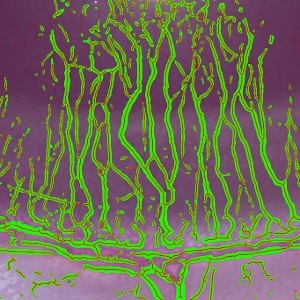

The classification identifies the entire vessel area within the region of interest. However, there is no straightforward way to translate the area for this complex structure into an estimate of length. Instead a skeletonization is applied after discarding all objects smaller than a (user-) defined limit. The skeletonize-step transforms the overlaying label to a 1-pixel wide structure by removing all pixels that do not belong to the midline (see FIGURE 2). From this, the total vessel length and individual segment lengths are calculated.